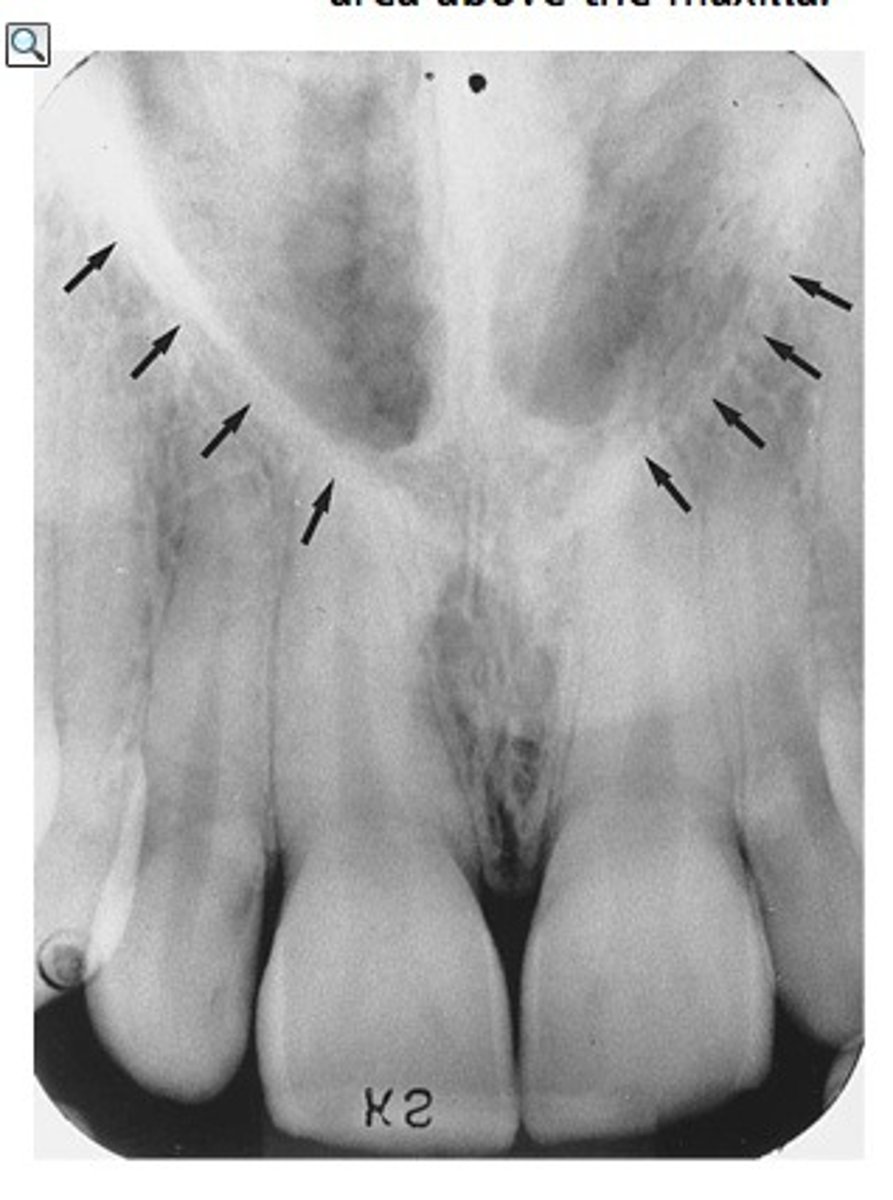

median suture

"crack" between roots of maxillary central incisors

area of incomplete fusion

radiolucent

incisive foramen

hole in the bone of the maxilla and between roots of incisors